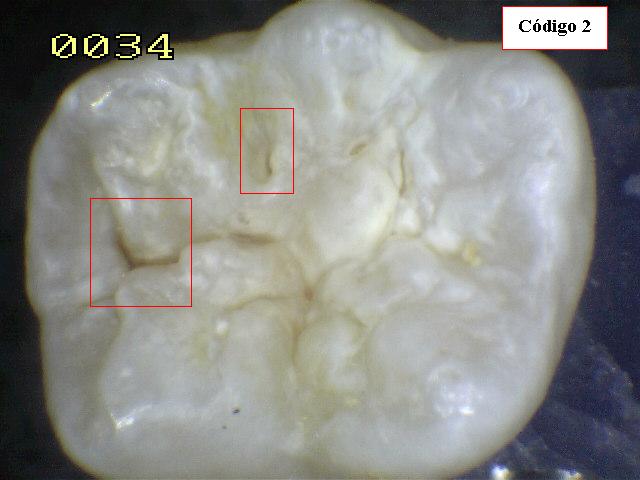

| CÓDIGO 2: Evidente cambio visual del esmalte

en estado húmedo y permanece después de secar. |

| Al observar el diente verá

una decoloración mancha

blanca o marrón en el fondo de la fosa y fisura y

que desborda hacia las paredes (más ancha que la fosa y fisura)

las manchas no tienen brillo y es consistente con desmineralización. |

Espécimen 5 |

| Corte sagital |

Verificando un código 1 histológico |